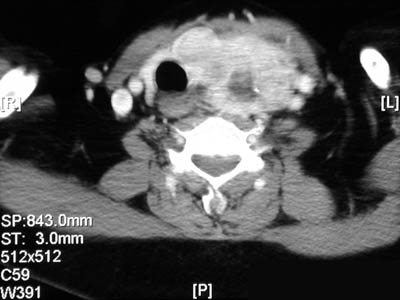

| The series of CT scans seen here demonstrate a large but asymmetric nodular goiter which involves the left lobe and produces marked displacement of the trachea to the right. In the views below, the goiter extends into the lower neck and down into the upper chest. Thus, a substernal location for a goiter is not impossible. |